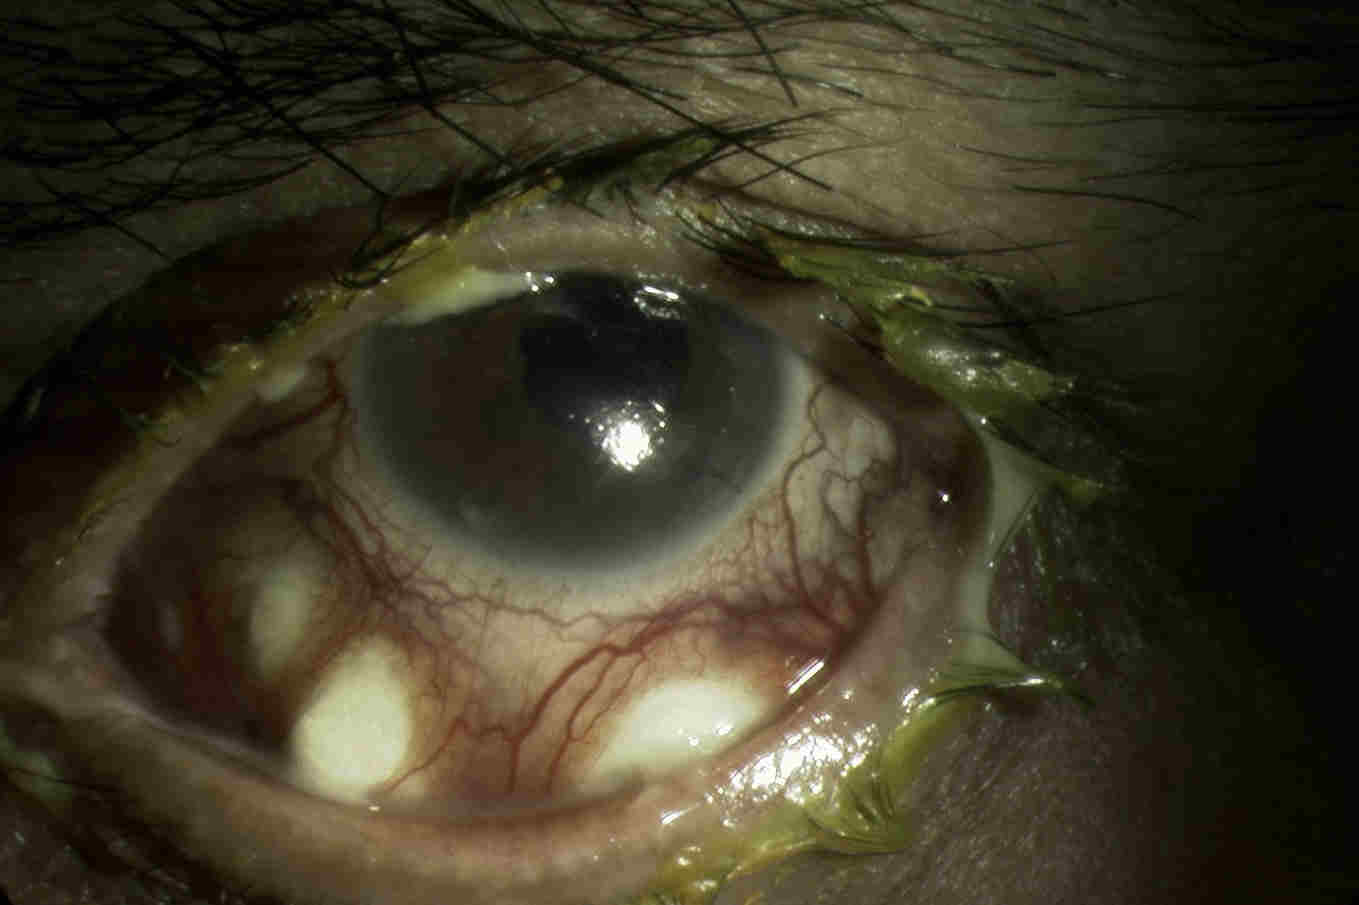

Fig. 3 Surgically induced necrotising scleritis following diabetic vitrectomy

Surgically-induced necrotising scleritis is a rare complication of surgery to the eye, particularly following pterygium excision, cataract surgery and scleral buckling3. A similar presentation may also occur following ocular trauma. Patients typically present with necrotising anterior scleritis, with the site of inflammation usually situated around the surgical wound. Presentation may be significantly delayed, ranging from day one to many years following surgery, with the mean around six months3.